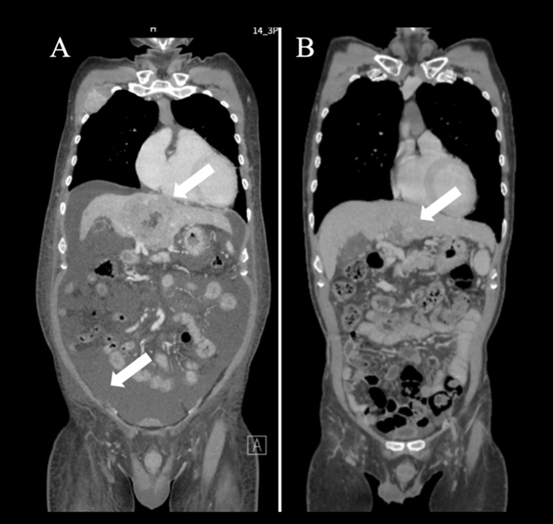

2024 年3 月《Cureus》期刊报道了一则IV期卵巢癌案例:一位 30 多岁的女性患者确诊时已出现双侧卵巢癌伴腹膜播散,同时存在肝、肺、骨多处转移,腹部有大量腹水,未接受手术和放疗,初始采用紫杉醇联合卡铂化疗方案。

治疗中,患者同步进行免疫治疗:从第18天起每两周注射 WT1-DC疫苗和纳武利尤单抗,通过红斑反应评估显示免疫激活良好。但因第 37 天腹水仍明显且 NK 细胞活性低,后续加入 NK 细胞治疗。

在第39、52、60天注射成熟NK细胞后,患者每次治疗后都出现高热,这是免疫系统被激活的信号。

第三次治疗后CEA、CA125指标明显下降,腹围减小,肝转移灶缩小。后续追加两次NK细胞治疗,142天后,PET-CT显示肺转移和腹膜播散消失,原发病灶显著缩小,患者计划进行根治性手术。治疗期间除发热外无其他副作用。